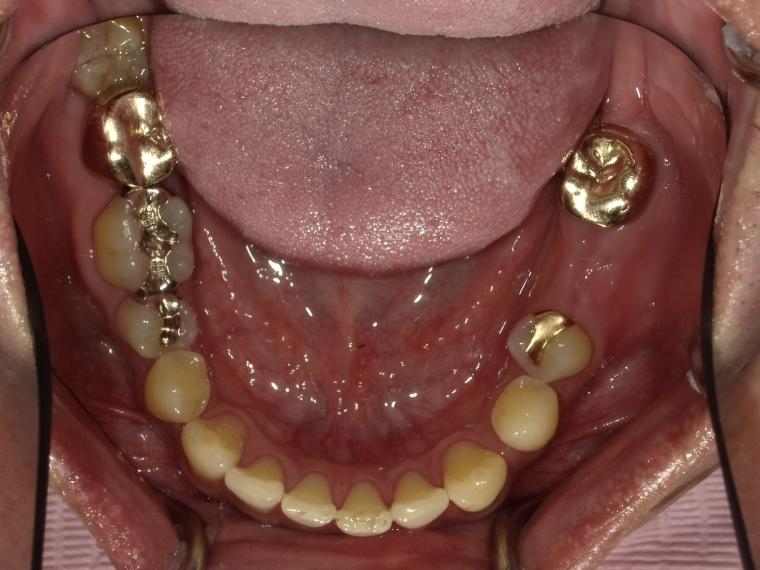

AFTER

44歳男性

/下顎1本欠損/インプラント埋込手術

インプラントでの治療を希望されて当院へご来院されました。

現在は定期検診で拝見させて頂いています。